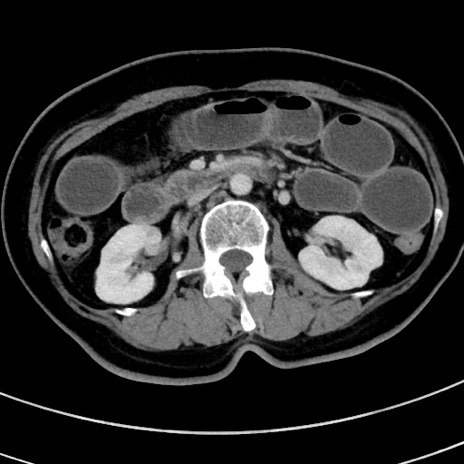

症例9(横断像)

【症例】 60歳代女性

【主訴】むかつき、みぞおちの痛み

【現病歴】3日前よりむかつきがあり、食事がとれない。

【既往歴】糖尿病

【身体所見】発熱なし、心窩部圧痛軽度あるも、腹膜刺激症状なし。

【データ】WBC 7400、CRP 1.92